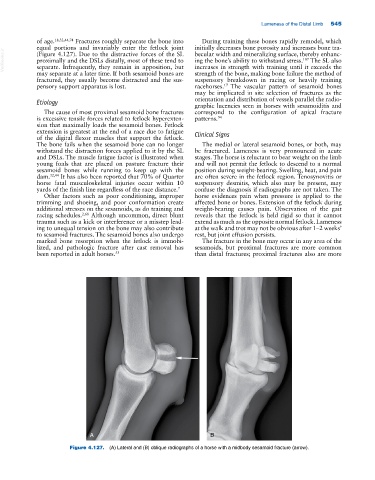

Figure 4.127. (A) Lateral and (B) oblique radiographs of a horse with a midbody sesamoid fracture (arrow).

of age. 18,32,44,74 Fractures roughly separate the bone into During training these bones rapidly remodel, which

(Figure 4.127). Due to the distractive forces of the SL